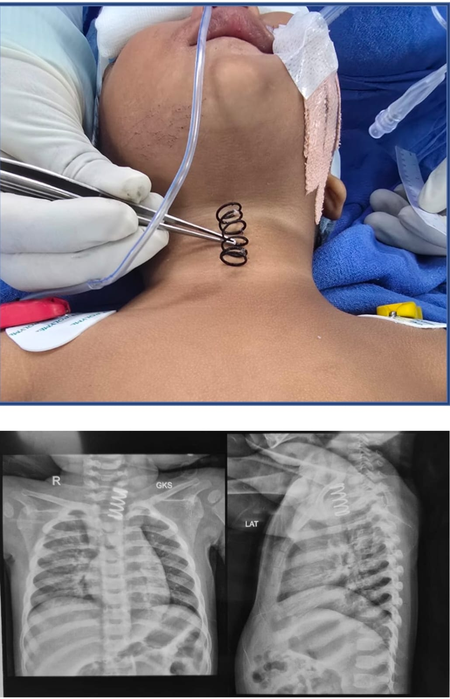

The metal spring stuck in the oesophagus, also known as the food pipe, was successfully removed after an endoscopic surgery, AIIMS said in an official statement.

“During the examination, an X-ray revealed a large metal spring lodged in the upper part of the child’s oesophagus,” AIIMS said, “with ulcerations extending along the mucosa”.

“The spring was stuck on the upper part of the food pipe. And the thickness of the spring was much more than the normal spring, which we see in our pens. It was approximately half an inch wide and at least 1.5 to 2 inches long,” Professor Dr. Vishesh Jain, from the Paediatric Surgery Department, told IANS.

Jain and his team used advanced endoscopic techniques in the operating room. The spring was carefully rotated and removed, preventing any perforation, the statement said.